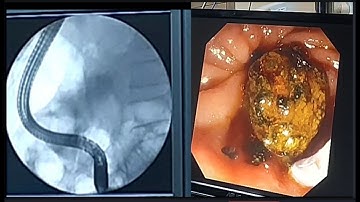

ERCP - Stone Extraction using a Stone Extraction Basket - EndoFlex GmbH - EN